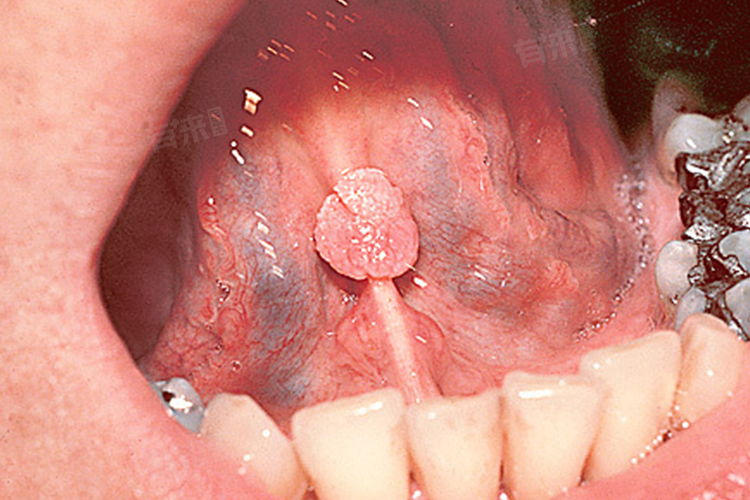

1、口腔科:口腔科医生专注口腔疾病诊疗,对口腔结构和病变熟悉。若怀疑口腔HPV感染,医生会详细检查口腔黏膜,查看有无异常增生物,如乳头状、菜花状肿物,或黏膜白斑、红斑等病变。通过口腔视诊、触诊,初步判断病变性质。对于口腔内明显的赘生物,口腔科医生可在局部麻醉下进行切除,并送病理检查,以明确是否为HPV感染导致的病变,为后续治疗提供依据。